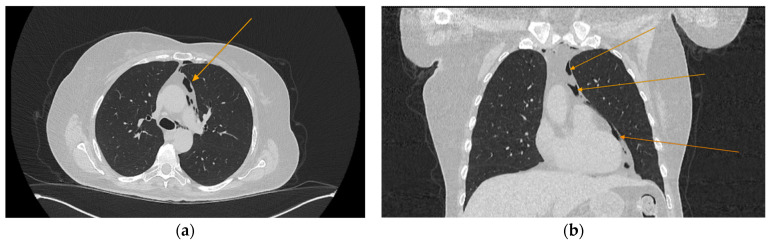

Background and Clinical Significance: Diabetic ketoacidosis (DKA) is a serious and potentially life-threatening condition, often triggered by infections or undiagnosed diabetes. Spontaneous pneumomediastinum (SPM) and pneumothorax are rare but recognized complications of DKA, possibly due to alveolar rupture from increased respiratory effort or vomiting. Sometimes, acute pancreatitis (AP) may further complicate DKA, but the co-occurrence of these three conditions remains exceptionally rare. Case Presentation: We describe the case of a 60-year-old woman without a known history of diabetes who arrived at the emergency department with abdominal pain, fatigue, vomiting, and altered mental status. Initial laboratory findings showed metabolic acidosis, hyperglycemia, and elevated anion gap, consistent with DKA. Imaging revealed spontaneous pneumomediastinum and subsequently a left-sided pneumothorax, without evidence of trauma or esophageal rupture. Epigastric pain, along with elevated serum lipase and CT findings, also confirmed acute pancreatitis. Despite the complexity of her condition, the patient responded well to supportive treatment, including oxygen therapy, fluid resuscitation, insulin infusion, and antibiotics. She was discharged in good condition after 28 days, with a confirmed diagnosis of type 2 diabetes, without further complications. Conclusions: This case highlights an unusual combination of DKA complicated by spontaneous pneumomediastinum, pneumothorax and acute pancreatitis in a previously undiagnosed diabetic patient. Because prompt intervention can lead to favorable outcomes even in complex, multisystem cases, early recognition of atypical DKA complications is critical in order to avoid misdiagnosis.